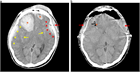

急性硬膜下血腫

1. 頭部外傷受傷直後から片麻痺等の神経症状や意識障害が持続する場合には、急性硬膜下血腫の存在を想起し呼吸・循環管理を行いつつ速やかに頭部CT撮影を行い診断する。

1. 抗血栓薬内服中の高齢者では軽微な外傷でも受傷することがあり、急速な意識障害の進行や亜急性の経過をとることもあり注意を要する。